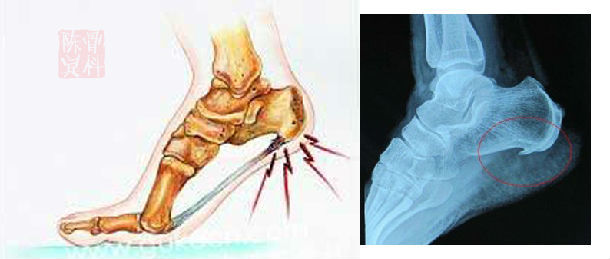

骨刺

在骨科疾病中,大多数都是因为肾气虚导致了骨质疏松,也有的表现为肾气外泄,比如骨质增生,虽然他们都是肾虚,肾气出了问题,但是治法却不一样。

针对大多数肾虚导致的骨质疏松,我们一般使用补肾的方式就可以解决。但是针对骨质增生导致的骨刺就要考虑其他因素了。

为什么会出现骨质增生,长骨刺?

中医认为肾气不够,肾阴虚,肾阳虚都会导致骨质疏松,也会导致骨质增生,两种肾虚疾病的产生都是因为肾气泻的太过,人体不能很好的保存津液,保护好体内的肾气。